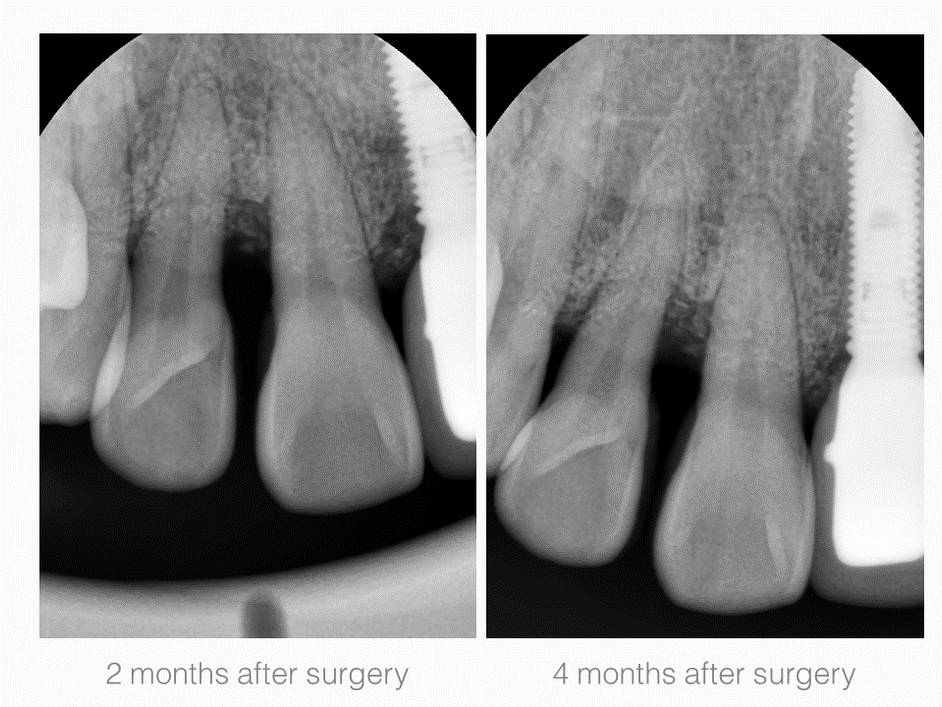

Periodontal Defects

2. Maxillary Lateral incisor